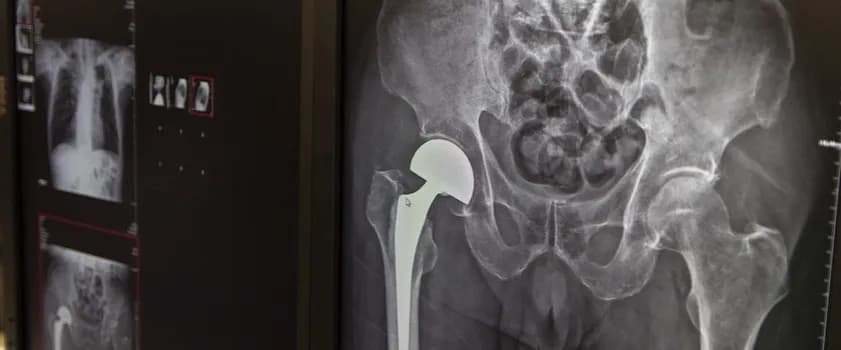

Endoprotezy stawu biodrowego refundowane przez NFZ dzielą się na dwa główne typy: cementowe i bezcementowe. System ochrony zdrowia zapewnia dostęp do obu rodzajów implantów, w zależności od indywidualnych potrzeb pacjenta. Wybór konkretnego typu protezy zależy głównie od wieku pacjenta, jakości kości oraz ogólnego stanu zdrowia. Obecnie refundacja operacji stawu biodrowego obejmuje w większości przypadków endoprotezy bezcementowe.

Kluczowa różnica między typami endoprotez biodra na NFZ tkwi w sposobie mocowania do kości. Protezy cementowe wykorzystują specjalny cement kostny, który tworzy stabilne połączenie między implantem a kością. Rozwiązanie bezcementowe bazuje na porowatej powierzchni implantu, umożliwiającej naturalne wroślnięcie się tkanki kostnej. Tego typu mocowanie zapewnia długotrwałą stabilność i jest preferowane u młodszych, aktywnych pacjentów.